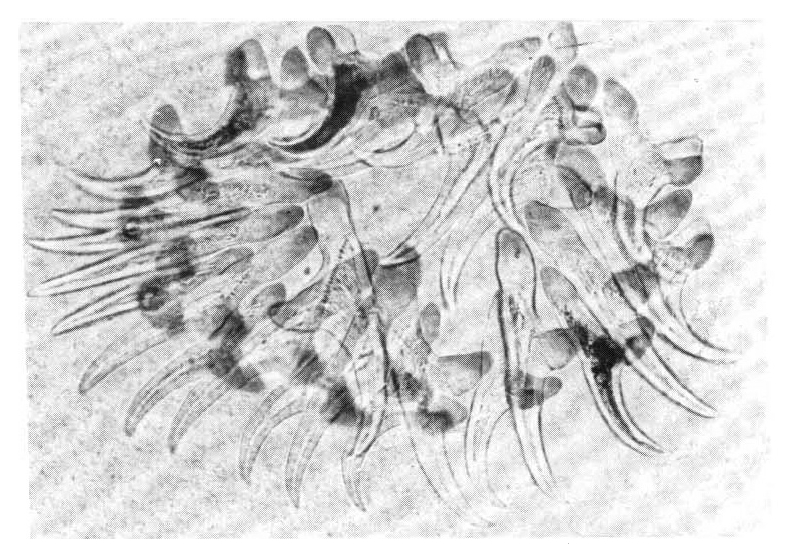

A biopsy of a subcutaneous nodule was done on the 4th hospital day, and upon microscopic examination, a bladder worm (Fig. 5)—its hooks (Fig. 6) and parenchymatous portion with spinal canal and separated bladder of the cysticercus (Fig. 7)—was observed. On the 12 th hospital day, the presence of cysticercus was confirmed by an open lung biopsy (Fig. 8).

Cross section of C. cellulosae shows the fully differentiated parenchymatous portion and the still separated bladder of the cysticercus.